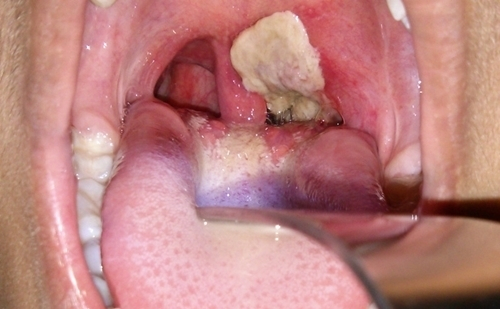

Biểu hiện bệnh có thể từ nhẹ đến nặng, thường có giả mạc màu trắng ở tuyến hạnh nhân, hầu họng, thanh quản, mũi, có thể xuất hiện ở da, các màng niêm mạc khác như kết mạc mắt hoặc bộ phận sinh dục, trường hợp nặng có thể gây biến chứng và tử vong.